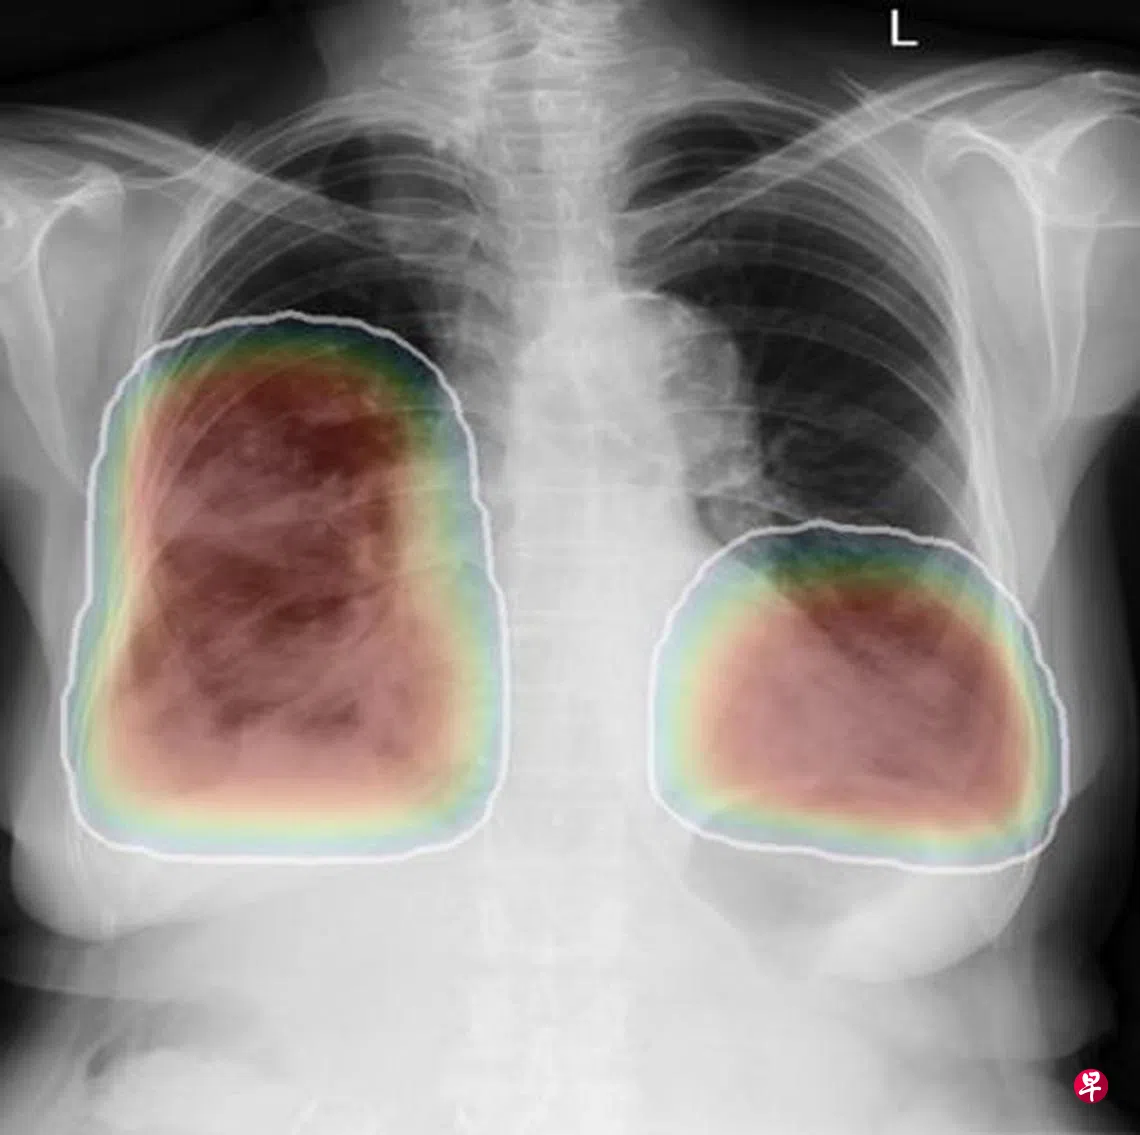

胸部X光是医生常用于检查胸腔及其周围器官状况的诊断方法,但病人通常要等上一到一个半小时,才能得知检查结果。这项利用人工智能的X光诊断技术,可根据影像异常的可能性高低,对病人进行排序,从而优先处理病情较为严重的个案,缩短等待时间至原来的一半。

据了解,芽笼综合诊疗所每月约有600名病人需要接受胸部X光检查。由于只有部分病人的X光报告会出现异常,新技术可优化医疗资源,更好地为病人服务。